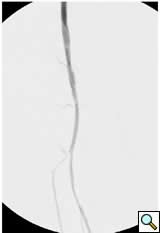

![]() |

Figure 1A: Angiogram |

Case 1: An 84-year-old male with rest pain, who had undergone prior revascularization with covered stents, represents with recurrent rest pain. The prior stents had come close to the origin of the SFA and at that time there had been some narrowing. Exposure was provided by performing a cut down and patching the CFA-proximal SFA to the level of the stents, following which gentle thrombectomy was performed, and a wire passed down. The angiogram demonstrated a distal lesion at the adductor canal which contributed to the thrombosis (Figure 1A). The patient underwent a day of lysis, following which cryoablation was used to treat the distal lesion (Figure 1B) and completion angiogram showed restoration of limb perfusion (Figure 1C).